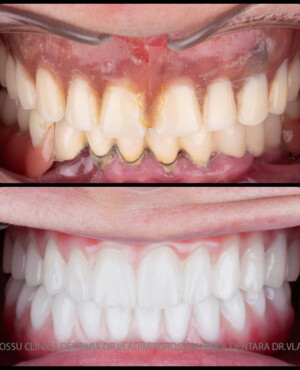

Această metodă este recomandată pacienților edentați total sau celor cu lipsuri dentare multiple. Procedura se realizează într-o singură etapă, iar pacientul primește proteza provizorie în ziua următoare intervenției. De regulă, proteza provizorie este realizată din masă plastică frezată. Suturile se îndepărtează după 5-7 zile.

La aproximativ 6 luni de la prima etapă, pacientul revine pentru protezarea definitivă. În această fază, medicul lucrează la nivelul multiunit-urilor și nu direct pe implanturi, ceea ce reduce riscurile pentru implant în etapa protetică.